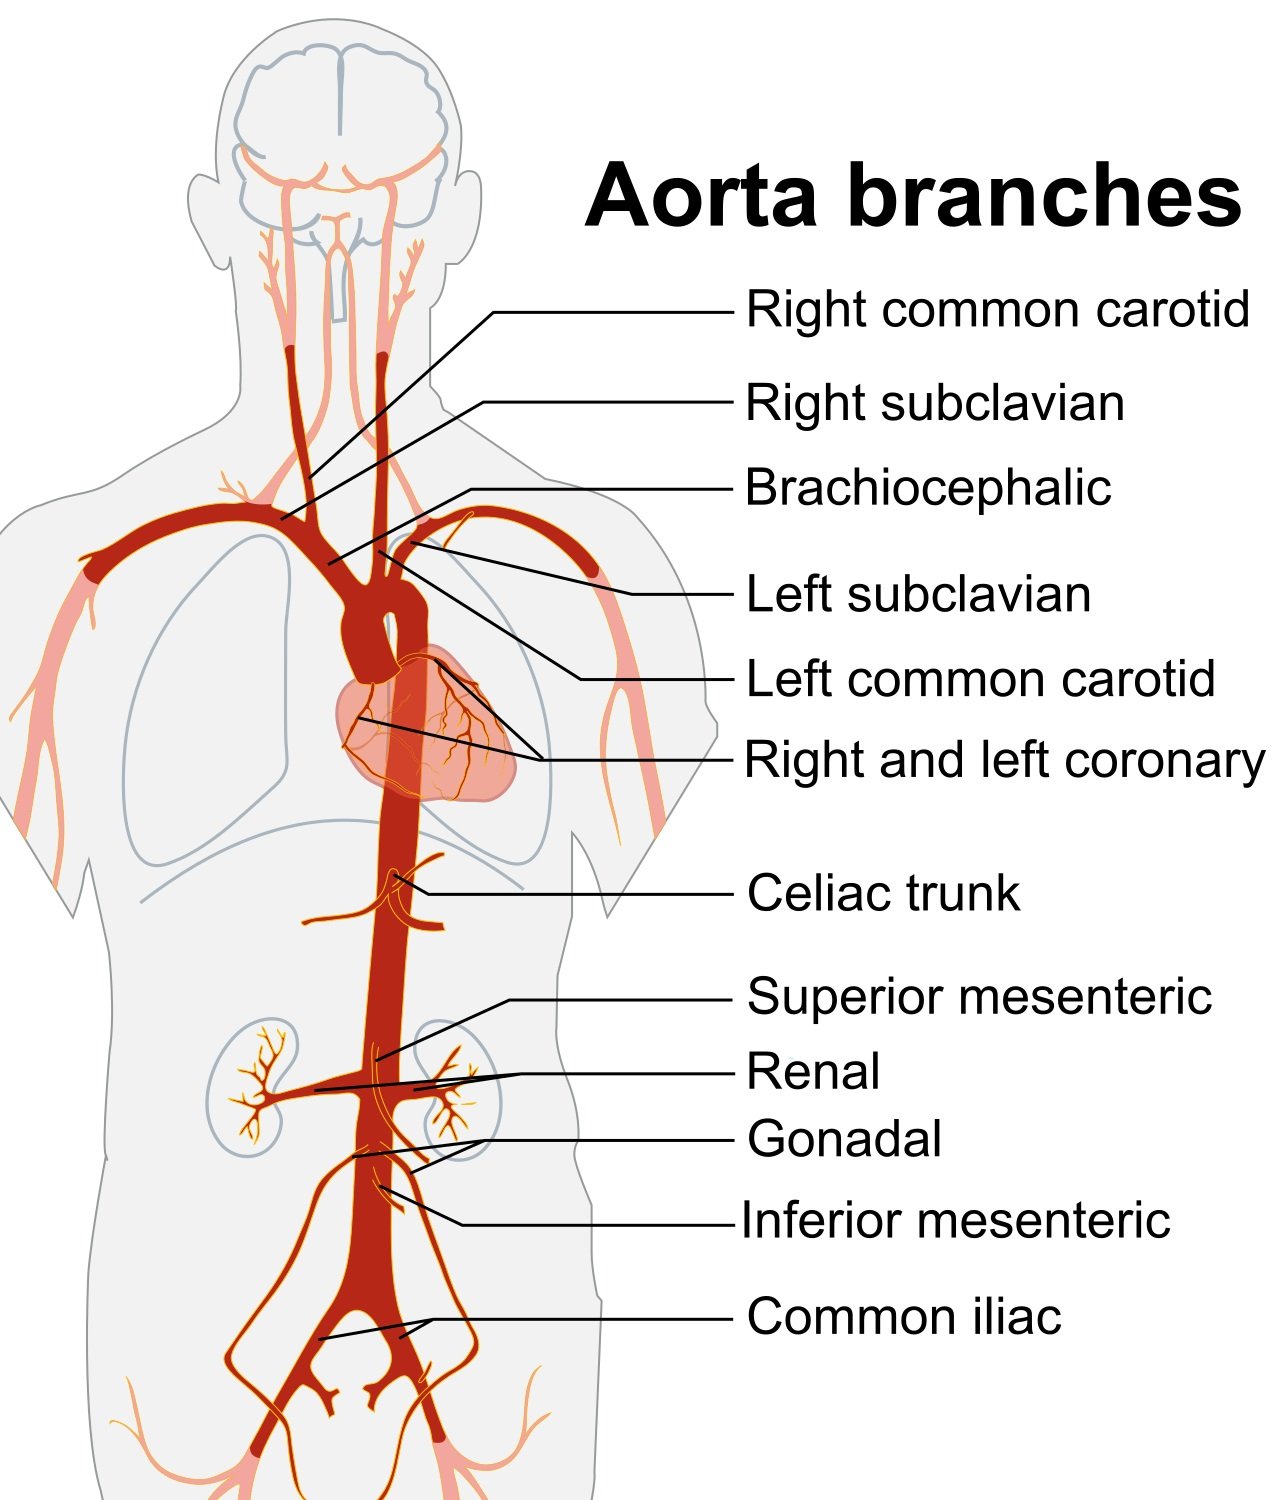

- Abdominal aorta lies slightly to left of midline and bifurcates at the level of the 4th or 5th lumbar vertebral body. (Illustration 1) The surface anatomy landmarks are the xiphoid process and the umbilicus (Illustration 2).

- Illustration 1. Overview of the abdominal aorta with major branches (Source: https://commons.wikimedia.org/wiki/File:Aorta_branches.jpg)